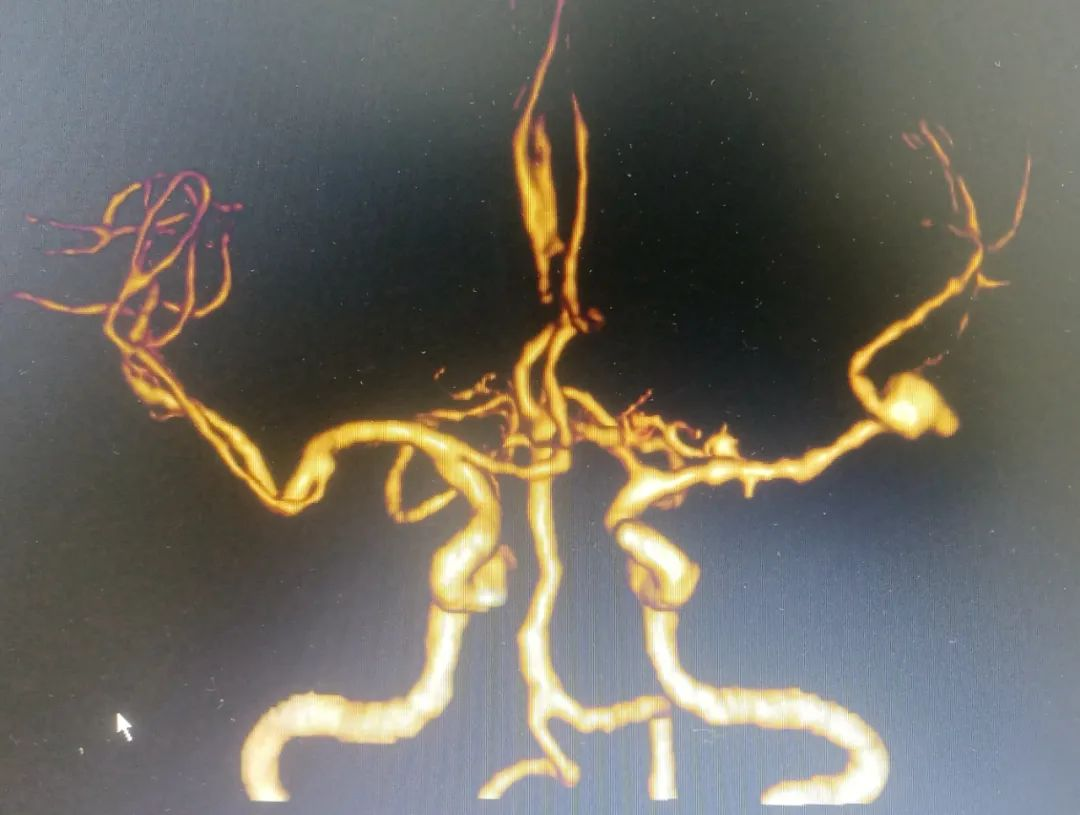

▲CT:左颞叶血肿

▲CTA:左侧大脑中动脉瘤,形态不规则

诊断明确,左颞叶血肿、蛛网膜下腔出血为左侧大脑中动脉分叉处动脉瘤破裂出血所致,病情危重,动脉瘤随时有再次破裂出血危及生命可能,我科手术团队立即展开病情讨论,结合患者病灶位置、动脉瘤形态、周围血管关系、经济等情况,综合评估后认为开颅动脉瘤夹闭术优于血管内介入治疗,经手术风险告知、签字同意后急诊实施开颅脑动脉瘤夹闭术。

因脑动脉瘤形态不规则、体积较大,且与周围血管分支关系密切,分离瘤体瘤颈极为困难,稍有不慎即可能动脉瘤再次破裂大出血。手术中手术团队精准、迅速找到病灶,谨慎分离瘤体,近端血流控制,找到瘤颈予夹闭。同时清除血肿,术中脑肿胀明显,予去掉骨瓣充分外减压,达到一举多得的效果。另外,开颅手术费用亦较介入手术费用大大减少。术后患者恢复良好,语言功能良好,无明显神经功能损伤,顺利出院。